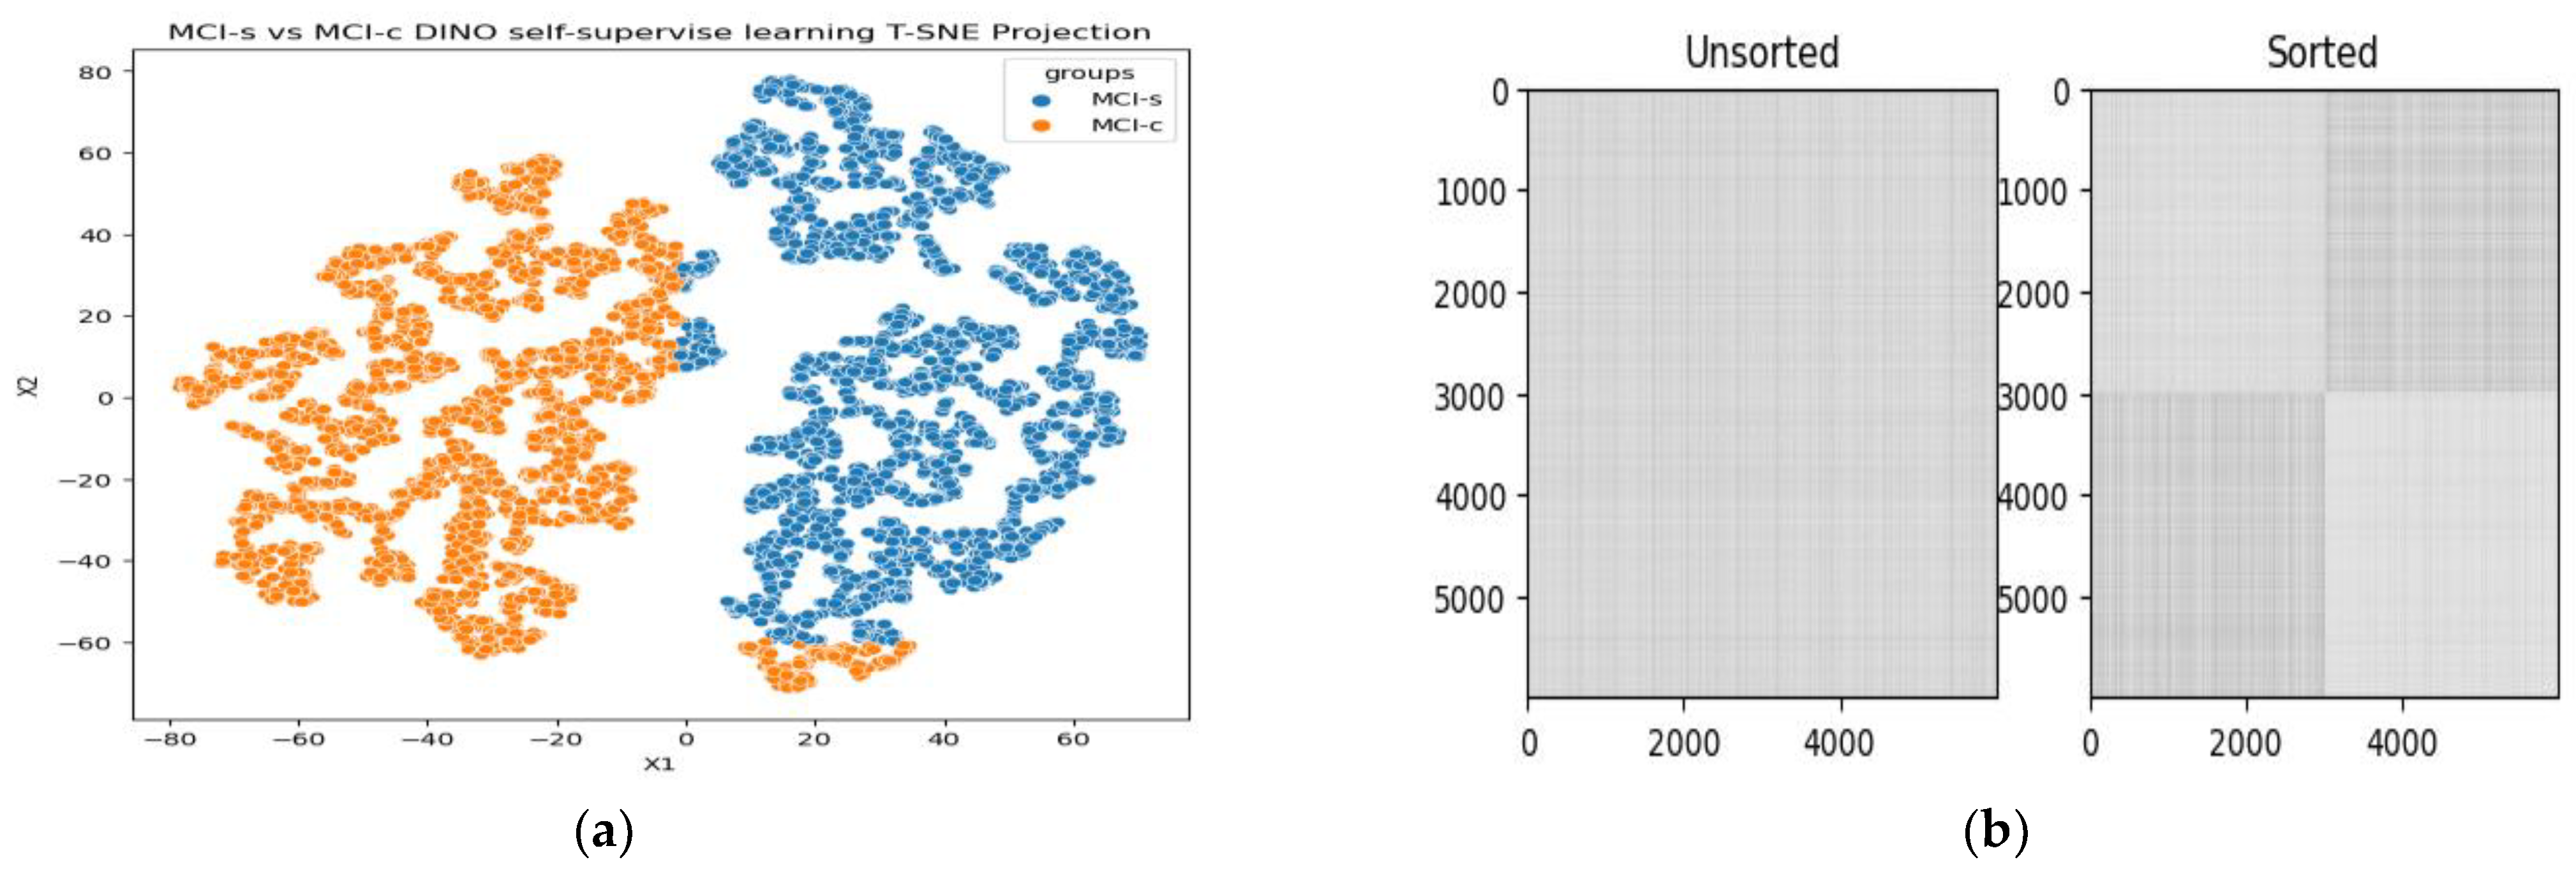

2.5. 18F-FDG-PET Feature Learning with ViT-Dino

3.1. Classification Performance on 18F-FDG-PET

3.2. Ablation Study